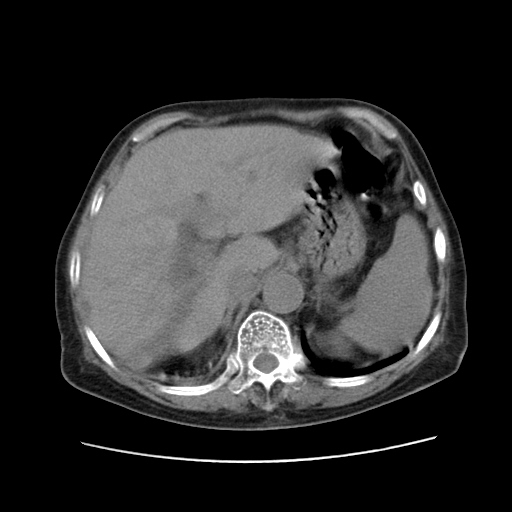

女,77.无不适

肝脏变异、异位胆囊,肝右叶肝内胆管结石并肝内胆管扩张。

肝右叶肝内胆管结石并肝内胆管扩张。

肝右叶肝内胆管结石并肝内胆管扩张

胆总管扩张

肝右叶肝内胆管结石并肝内胆管扩张。胆总管下段梗阻,考虑壶腹部占位。

右侧肝内胆管局限性扩张,其内密度不均匀,扩张的胆管壁增厚,考虑肝内胆管炎合并结石可能性大

肝右叶肝内胆管结石并肝内胆管扩张。胆总管下段梗阻,考虑壶腹部占位。支持